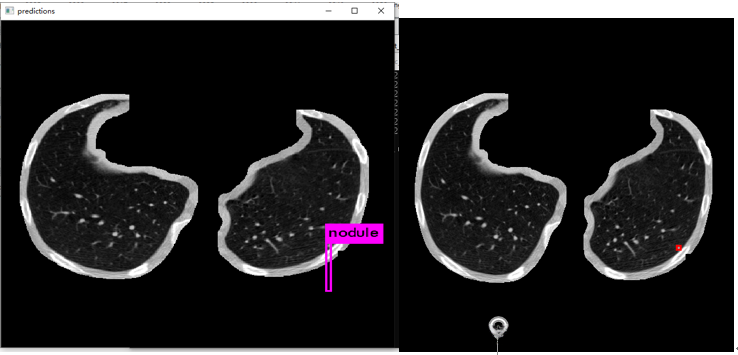

更新: 2019.9.23

修改anchor size后重新训练

对数据集进行kmean 是聚类,修改anchor size,这里需要主要几点:

基于标注生成的标注图像,在实际应用中无法获取到发现肺结节的bounding boxes大致呈现比例为1:1。然而,在yolov3算法中由于采用了3 个特征尺度来进行位置预测,在此处我们选择聚类中心的数量定为**3。

通过反复进行多次聚类运算,可以获得较为合适的anchor大小(但有时可能出现不收敛的情况,并导致计算出现问题):

这个之84.07%已经很高了,比voc 67%左右高出不少。

训练:

检测效果: